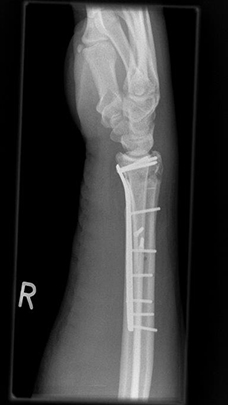

Komplexe rechtsseitige Unterarm-Handgelenksfraktur eines rechtshändigen jungen Mannes. Nach CT-Untersuchung offene Reposition und Rekonstruktion der komplexen Fraktursituation mit angepasster Plattenlänge. Sehr gute Funktion im weiteren Verlauf nach achsengerechter Ausheilung.